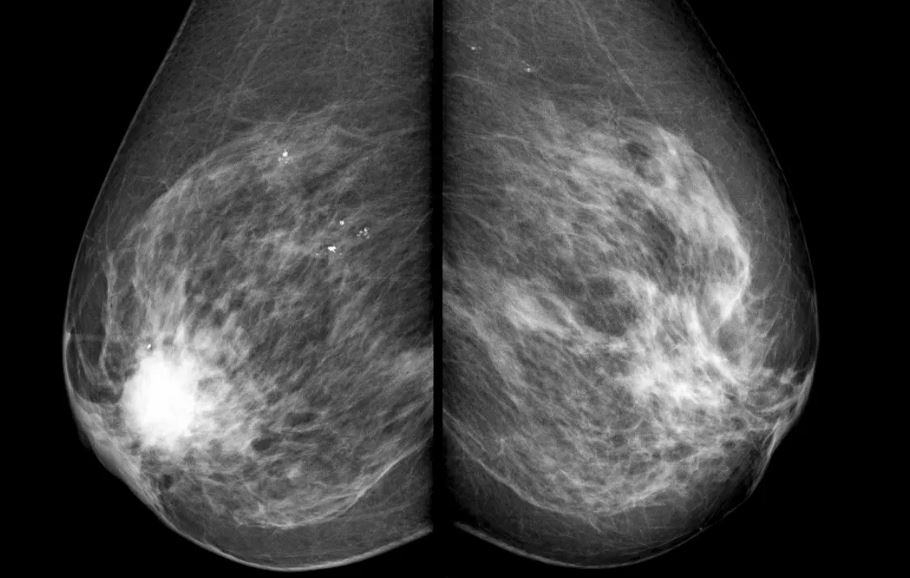

İsviçre mamografiyi yasakladı

İsviçre, mamografiyi yasaklayan ilk ülke oldu ve tıp tarihinin en büyük sahtekarlıklarından birinin ardındaki gerçeği ortaya çıkardı.

Kadınlar onlarca yıldır iyileştirmek için değil, kâr etmek için tasarlanmış bir sistem tarafından terörize edildi, yanlış teşhis konuldu ve sakat bırakıldı. Artık maske düştü. Mamografi asla hayat kurtarmayı amaçlamıyordu.